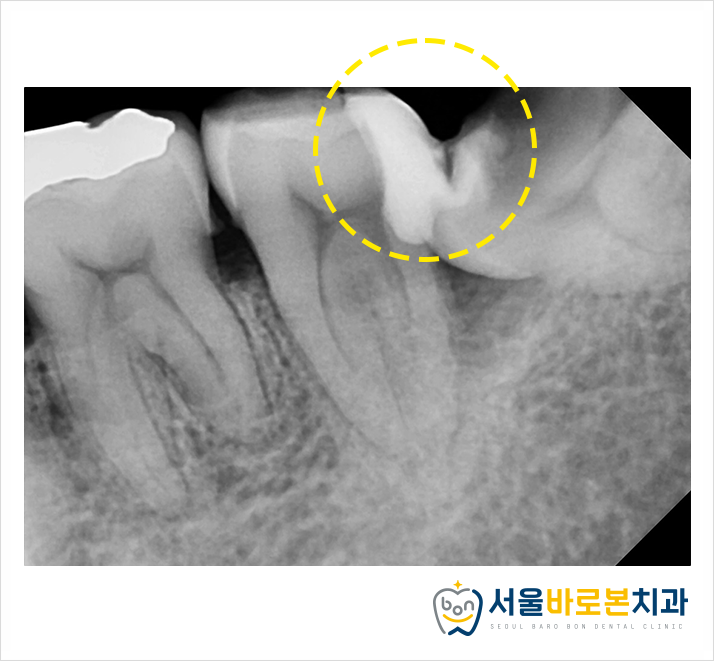

우선 왼쪽 아래 사랑니

발치를 먼저 진행하기로 했습니다.

사랑니는 충치가 너무 심해

이미 삭아 구멍이 뻥

뚫려 있는 상황이었는데요.

저희 치과에 내원하신 첫날,

왼쪽 아래 큰 어금니의

완벽한 신경치료 과정을 위해서

옆면의 충치를 제거한 직후의 사진입니다.

사랑니 옆면의 충치도

가능한 출혈이 발생하지 않도록

조심스럽게 제거해주었답니다.